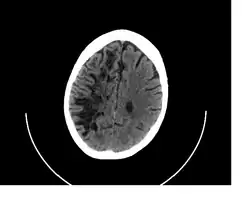

A perivascular space, also known as a Virchow–Robin space, is a fluid-filled space surrounding certain blood vessels in several organs, including the brain,[1] potentially having an immunological function, but more broadly a dispersive role for neural and blood-derived messengers.[2] The brain pia mater is reflected from the surface of the brain onto the surface of blood vessels in the subarachnoid space. In the brain, perivascular cuffs are regions of leukocyte aggregation in the perivascular spaces, usually found in patients with viral encephalitis.

In humans, perivascular spaces surround arteries and veins can usually be seen as areas of dilatation on MRI images. While many normal brains will show a few dilated spaces, an increase in these spaces may correlate with the incidence of several neurodegenerative diseases, making the spaces a topic of research.[4]

Perivascular spaces are most commonly located in the basal ganglia and white matter of the cerebrum, and along the optic tract.[13] The ideal method used to visualize perivascular spaces is T2-weighted MRI. The MR images of other neurological disorders can be similar to those of the dilated spaces. These disorders are:[7]

Perivascular spaces are distinguished on an MRI by several key features. The spaces appear as distinct round or oval entities with a signal intensity visually equivalent to that of cerebrospinal fluid in the subarachnoid space.[7][14][15] In addition, a perivascular space has no mass effect and is located along the blood vessel around which it forms.[14]